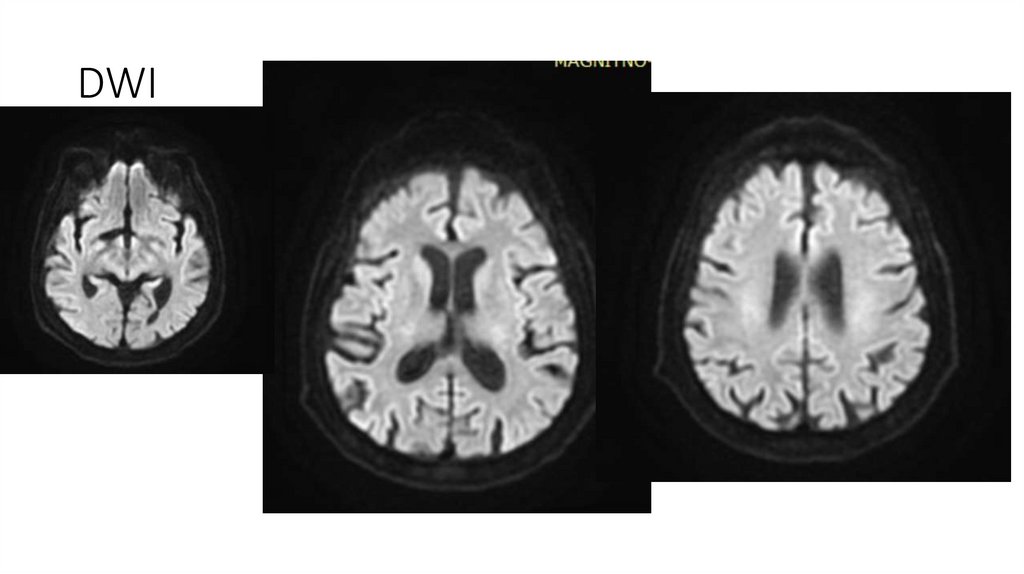

18. МРТ ГМ от 08.04.2025

Описание

-Срединные структуры не смещены.

-Желудочки обычной формы и размеров.

-Субарахноидальные пространства не расширены.

-Дифференциация серого и белого вещества сохранена.

-В белом веществе головного мозга, в паравентрикулярных и конвекситальных областях визуализируются множественные очаги

диаметрами 3-10мм, вероятно, сосудистого генеза.

-Отмечается незначительное расширение периваскулярных пространств.

-МР-сигнал от подкорковых ядер не изменен.

-Селлярная область без патологических изменений.

-Размеры гипофиза в пределах нормы.

-Стволовые структуры и мозжечок в пределах нормы.

-Мостомозжечковые углы без особенностей.

-Краниовертебральный переход не изменен.

-Придаточные пазухи и ячейки сосцевидных отростков воздушны.

-Содержимое глазниц без особенностей. ;

Заключение

• МР-картина множественных очагов в белом веществе головного мозга, вероятно,

сосудистого генеза.

22. DWI